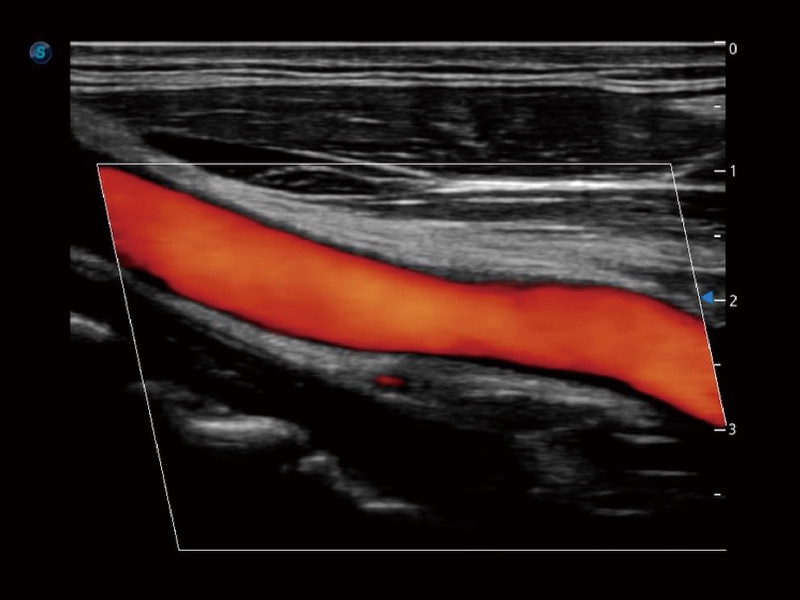

• SR Flow 高分辨率血流成像技术

高分辨率血流成像技术提高了对低速血流信号的检测能力。在提高空间分辨率的同时,也克服了血流外溢现象,为用户提供更加真实的血流动力学信息。

• 血管内中膜自动测量 Auto IMT

血管内中膜的厚度值是预测心血管疾病风险的重要指标,Auto IMT可以实现血管近场和远场内中膜厚度的自动测量,为临床提供快捷有效的诊断工具。

临床图